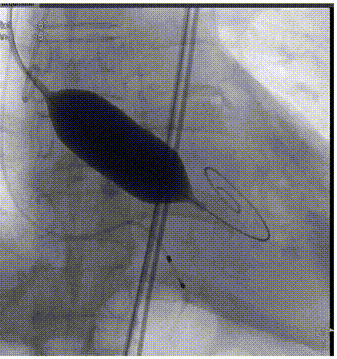

瓣膜定位

瓣膜脱钩

全息剪影

术后超声心动图提示:主动脉瓣人工瓣膜术后压差从61mmHg降至5mmHg,前向血流速度从4.8m/s降至1.6m/s,微量反流,左室壁搏幅正常范围,手术效果良好。